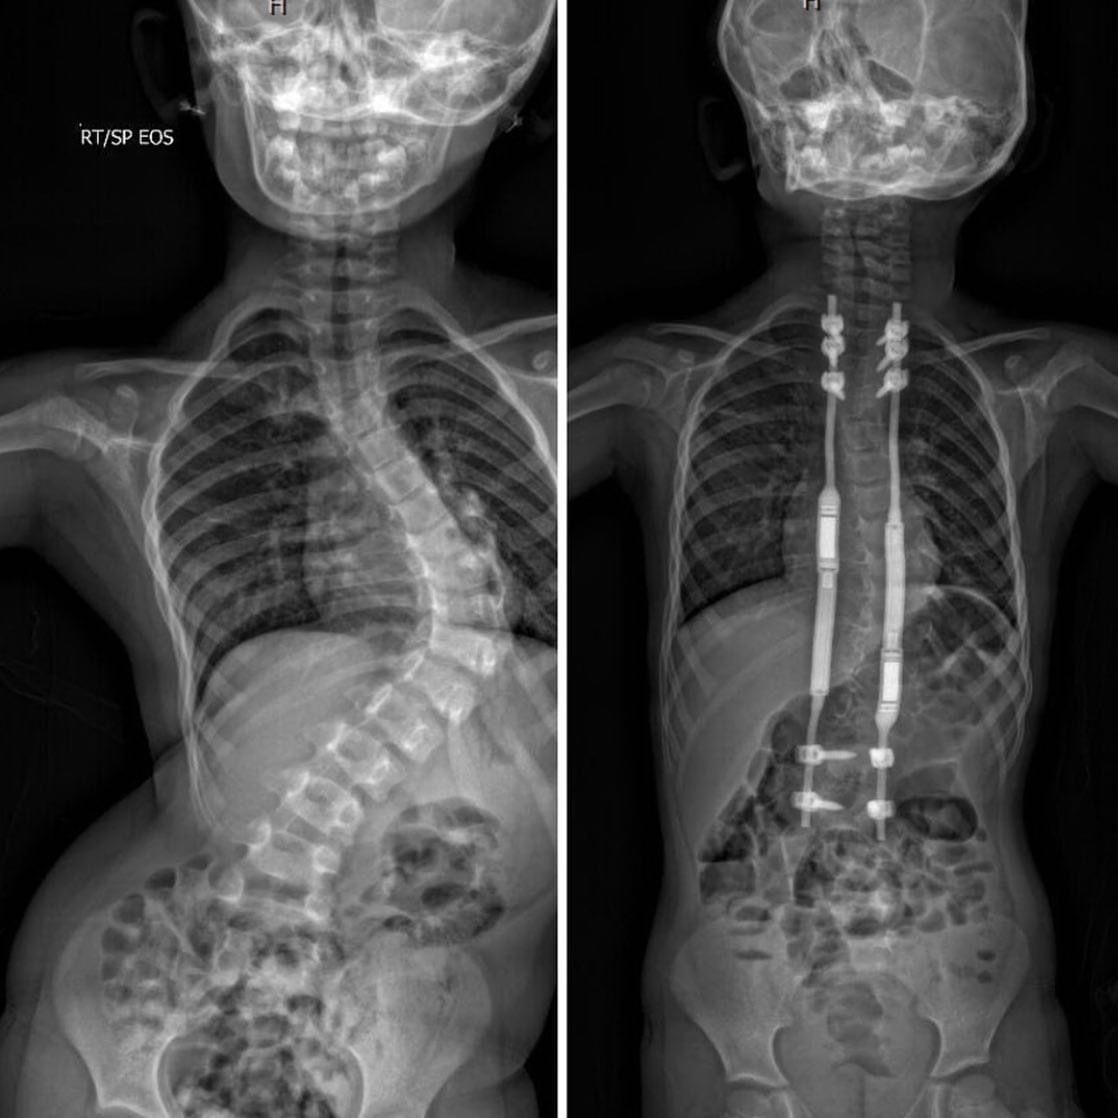

Idiopathic EarlyOnset Scoliosis Treated With Magec Rods What to Do Magic Rods For Scoliosis In this treatment system, a spine surgeon will. Magec (magnetic expansion control) growing rods are used to treat children with significant spinal curvature resulting from scoliosis. Magec growing rods are a new surgical treatment for children with severe spinal deformities that uses implantable rods and an external remote. These growing rods use a magnetic remote. In this review, we examine. Magic Rods For Scoliosis.

Idiopathic EarlyOnset Scoliosis Treated With Magec Rods What to Do Magic Rods For Scoliosis In this treatment system, a spine surgeon will. Magec (magnetic expansion control) growing rods are used to treat children with significant spinal curvature resulting from scoliosis. These growing rods use a magnetic remote. After the initial procedure to implant the rod,. In this review, we examine the results from clinical, radiological and explant studies following the use of magec, in. Magic Rods For Scoliosis.